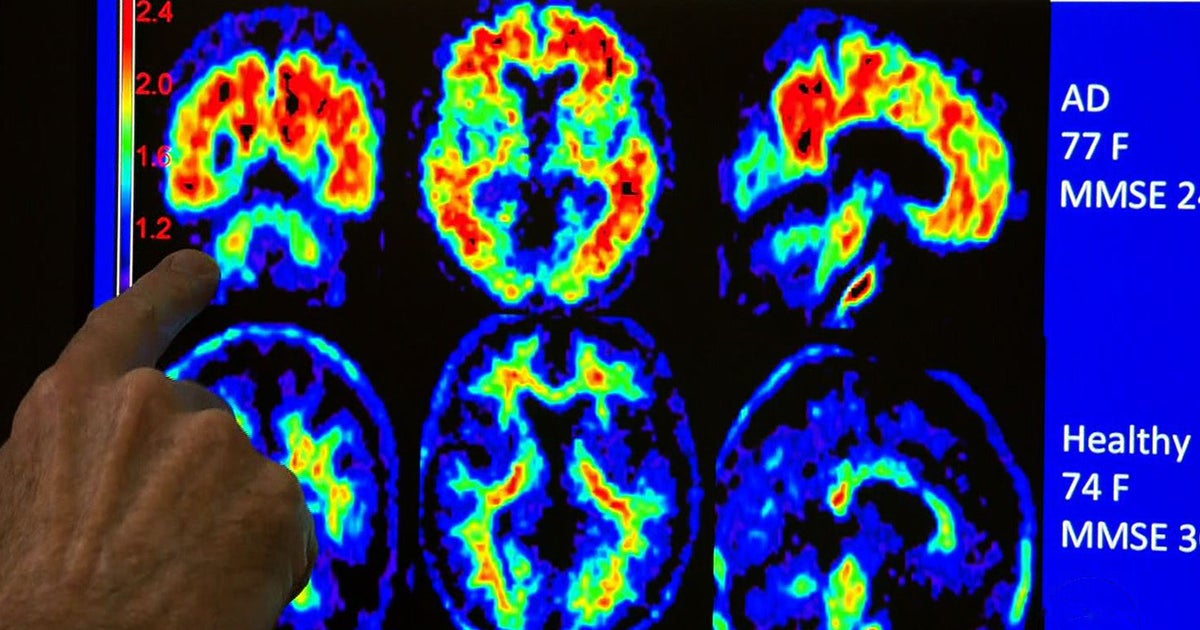

Alzheimer's breakthrough as experts discover 'HOW to control plaques buildup in the brain

Experimental ultrasound treatment targets Alzheimer's brain plaque CBS News How Does Plaque Build In The Brain cerebral amyloid angiopathy (caa) happens when amyloid (abnormal) proteins build up in blood vessels in your brain. When microglia fail to clear. scientists find brain's immune cells form some plaques as a defense in alzheimer's, suggesting a new therapeutic. A type of glial cell called microglia engulfs and destroys waste and toxins in a healthy brain. cerebral. How Does Plaque Build In The Brain.